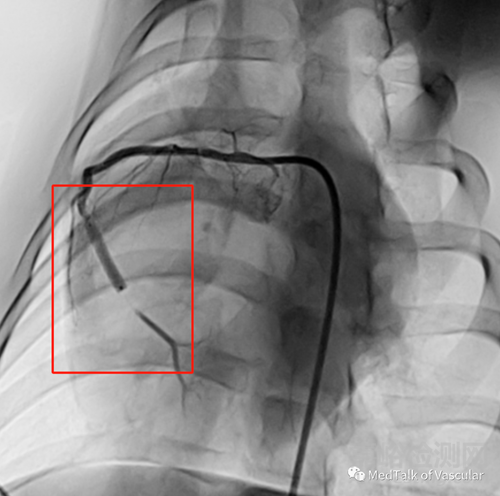

4)更安全、更舒適:自灌注藥球擴張時,將導(dǎo)絲撤回到近端MARK點后,血液通過導(dǎo)絲腔到達遠端,不完全阻斷血流,患者更安全更舒適。如下圖:造影圖顯示遠端有血液;

圖5,恒言®自灌注藥球造影圖

5)更有效:相較于其他藥球擴張時堵塞血流,恒言®自灌注藥球擴張時遠端有15%的血液通過,可以增加擴張時間,降低血管彈性回縮,提高紫杉醇藥物的轉(zhuǎn)移率,藥物釋放更充分,治療更有效;